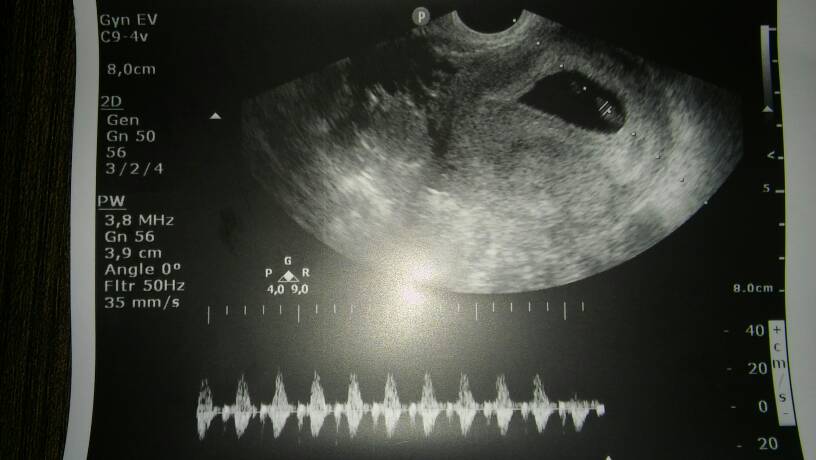

Cześć dziewczyny :) zdjęcia usg z 13.03:) wg daty ostatniej miesiączki powinien być 10 tydz jest 9 :) serduszko pięknie bije <3

17310649_1665941770089855_1249577253_o.jpg

17311407_1665941826756516_410371067_o.jpg

79,9 KB · Wyświetleń: 1 351

94,1 KB · Wyświetleń: 1 522